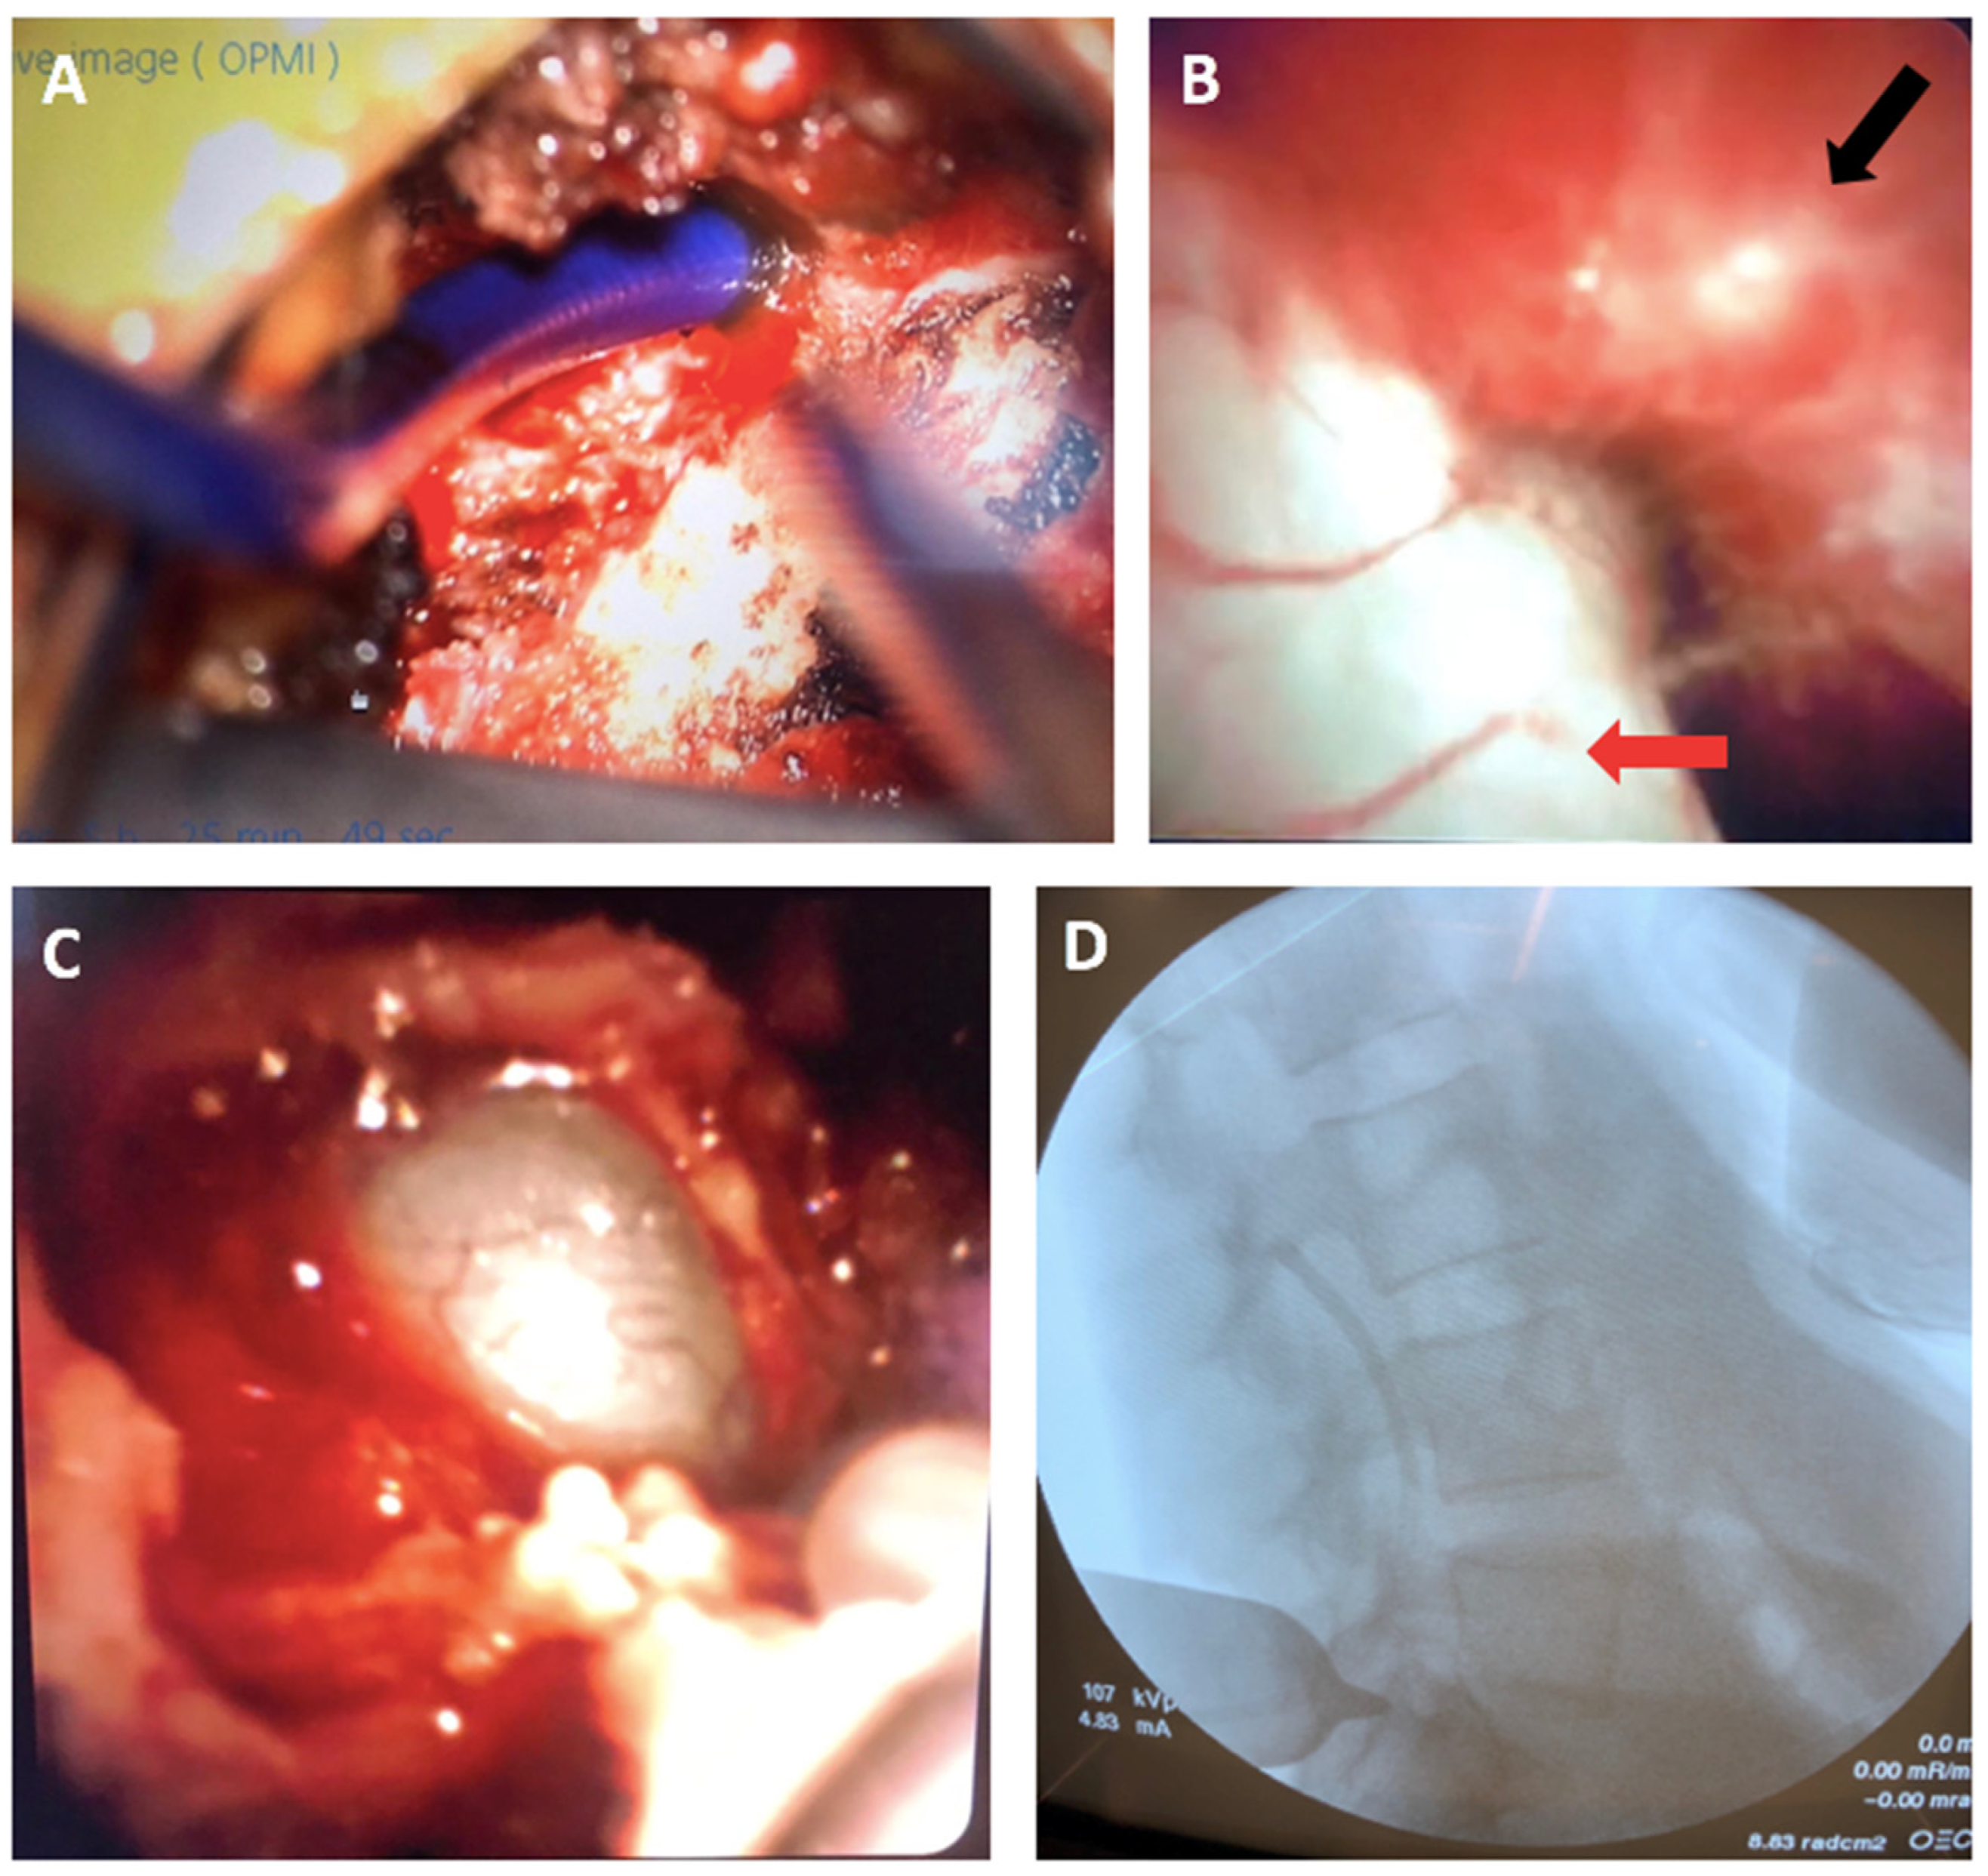

4.2. Novel Surgical Approach

4.3. Postoperative Outcomes